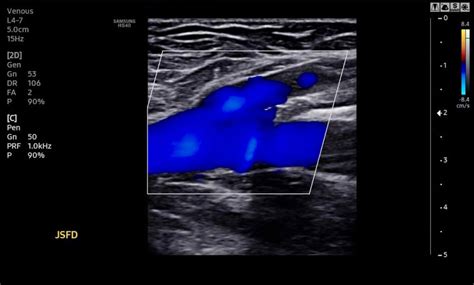

Durante o exame, o técnico aplica um transdutor, ou cabeçote, na pele do paciente. Este dispositivo emite e capta as ondas sonoras, que são processadas pelo aparelho e transformadas em imagens em tempo real. O profissional acompanha o exame de perto, ajustando os parâmetros do aparelho e posicionando o transdutor para obter imagens de alta qualidade.

Após a realização do ultrassom, o técnico interpreta as imagens e elabora um relatório que é encaminhado ao médico responsável pelo paciente.